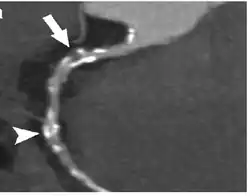

Coronary computed tomography angiography (CCTA)

Computed tomography angiography (CTA) is an imaging methodology using a ring-shaped machine with an X-ray source spinning around the circular path so as to bathe the inner circle with a uniform and known X-ray density. Cardiology uses are growing with the incredible developments in CT technology. Currently, multidetector CT, specially the 64 detector-CT are allowing to make cardiac studies in just a few seconds (less than 10 seconds, depending on the equipment and protocol used). These images are reconstructed using algorithms and software.

Coronary CT calcium scan

A coronary CT calcium scan is a computed tomography (CT) scan of the heart for the assessment of severity of coronary artery disease. Specifically, it looks for calcium deposits in the coronary arteries that can narrow arteries and increase the risk of heart attack.[17] This severity can be presented as Agatston score or Coronary Artery Calcium (CAC) score. The CAC score is an independent marker of risk for cardiac events, cardiac mortality, and all-cause mortality.[18] In addition, it provides additional prognostic information to other cardiovascular risk markers.[18] A typical coronary CT calcium scan is done without the use of radiocontrast dye, but it can possibly be done from contrast-enhanced images as well, such as in coronary CT angiography.[19]